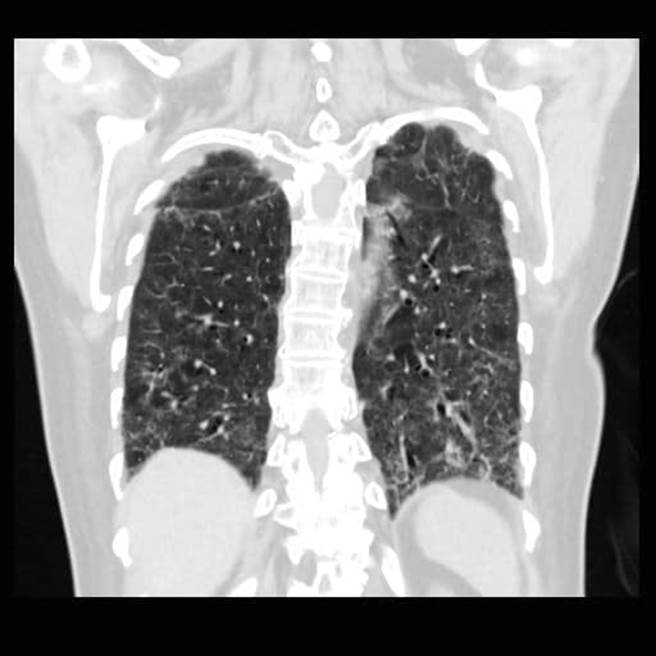

许多民眾仍在挑疫苗厂牌打,苏一峰分享肺纤维化的照片,再度呼吁民眾,若不想染疫得重症,就改快去打疫苗。(图/翻摄自苏一峰脸书)

英国研究指出,无论接种哪个厂牌的疫苗,都能大幅降低重症机率,但仍有不少民眾坚持要挑疫苗。对此,胸腔科医师苏一峰分享,院内自己人出现「肺纤维化」的情况,无法脱离氧气罩,让他看了很难过,也再度呼吁大家,如果不想要重症「肺纤维化」,就赶快去打疫苗,恐怖照片也引起网友们讨论。

苏一峰今在脸书发文分享,新冠肺炎重症之后,导致患者肺纤维化,现在无法脱离氧气罩,这个状况出现在院内自己人身上,真的看了很难过。并再度呼吁大家,不想要肺纤维化就赶快去打疫苗,属于高危险的医护人员也快点打。